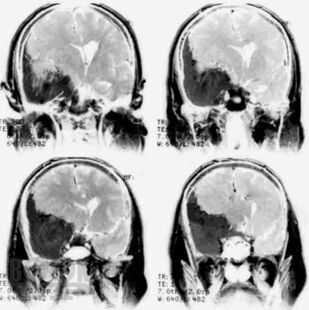

Первичные опухоли головного мозга

Кратко изложены этиология, особенности эпидемиологии, патогенеза, классификация и основные клинические проявления первичных опухолей головного мозга, современные принципы клиники, диагностики и оказания госпитальной помощи больным с данной патологией. Представлены алгоритмы обследования и лечения больных с наиболее часто встречающимися опухолями в зависимости от стадии течения патологического процесса.